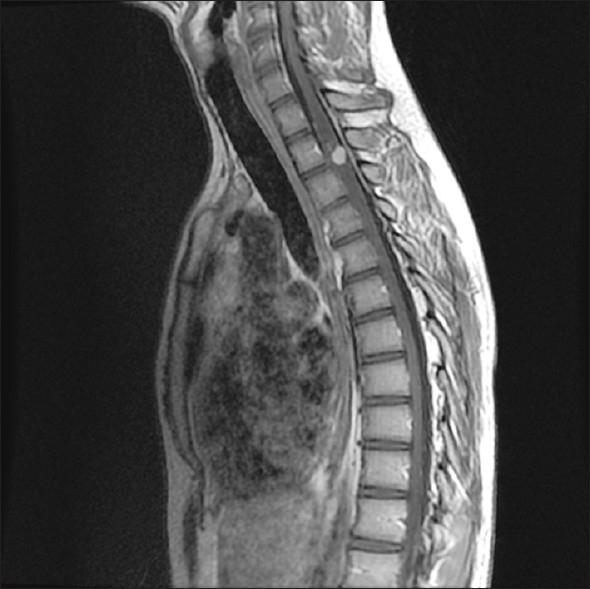

Seventeen patients underwent microsurgical resection of 20 spinal HBs at the Department of Neurosurgery at Helsinki University Central Hospital (HUCH). Thirteen tumors were in the cervical spine, five in thoracic and one patient had two lumbar lesions. MRI tumor showed an associated syrinx in 16 patients (94%). Tumor volume ranged from 27 to 2730 mm(3). Out of 17 patients, 11 (65%) tested positive for VHL in mutation analysis. Five of these patients with tumors ranging from 55 to 720 mm(3) were treated prophylactically.

17例患者在赫尔辛基大学中心医院(HUCH)神经外科接受了20例脊髓HB的显微手术切除。13个肿瘤位于颈椎,5个位于胸椎,1例患者有2个腰椎病变。MRI检查显示16例患者(94%)伴有脊髓空洞症。肿瘤体积为27至2730立方毫米。在17例患者中,11例(65%)在突变分析中VHL检测呈阳性。其中5例肿瘤体积为55至720立方毫米的患者接受了预防性治疗。